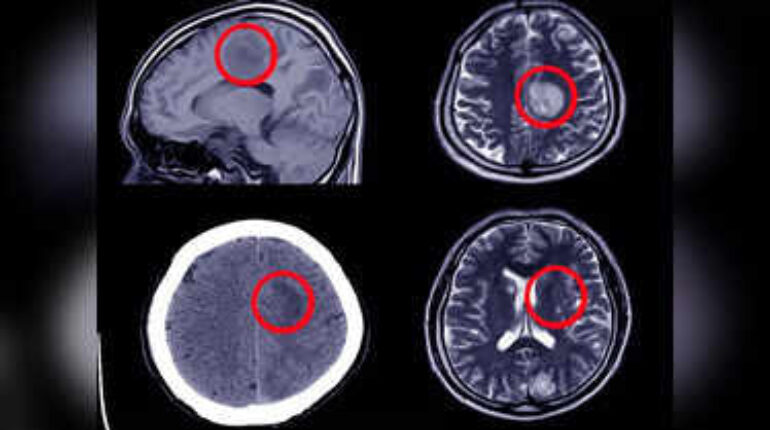

A brain aneurysm occurs when a weakened blood vessel in the brain bulges or balloons, creating dangerous…